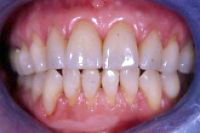

Die Abb. 1 bis 4 sollen als anschauliche Beispiele für gesunde und kranke Fundamente dienen.

Ein 31 Jahre alter Patient zeigt einen starke Zahnfleisch-Rückgang im Oberkiefer (Abb. 1 und 3) und wir beschliessen, diese Rezessionen zu behandeln.

Der Erfolg der Behandlung ist deutlich in den Abb. 2 und 4 zu sehen. Sehr augenfällig konnte die Situation um den Eckzahn im linken Oberkiefer verbessert werden (vergleiche dazu Abb. 3 vorher und Abb. 4 nachher).